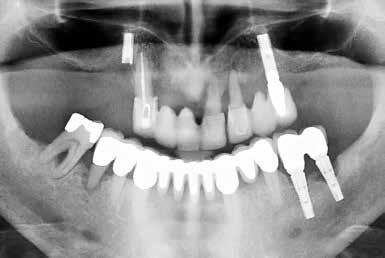

Ikke alle mennesker er egnede til at få implantater

Hvis en implantatbehandling skal lykkes på langt sigt uden, at der opstår periimplantitis, afhænger det i lige så høj grad af det forarbejde, der ligger før selve behandlingen, som af den kirurgiske teknik. Korrekt patientselektion og grundig forberedelse er nøglen til implantater, der holder i mange år.

En succesfuld implantatbehandling begynder længe før selve kirurgien. Ikke alle patienter er egnede til at få implantater ved første konsultation, og i mange tilfælde kræver det en grundig vurdering af både lokale forhold i mundhulen og patientens generelle helbred, før man kan foretage et sikkert valg.

- Langtidsholdbare implantater afhænger i høj grad af denne indledende vurdering, da den giver klinikeren mulighed for at identificere risikofaktorer, som senere kan føre til biologiske komplikationer omkring implantatet, forklarer tandlæge og ph.d. Kristina Bertl, der har et indgående kendskab til parodontologi.

Hold øje med risikofaktorer

Men hvad er det for nogle risikofaktorer, man skal holde øje med? Ifølge Kristina Bertl bør man tidligt identificere forhold som utilstrækkelig mundhygiejne, ubehandlet parodontitis, rygning, systemiske sygdomme og medicin, der kan påvirke knogleheling og vævsrespons.

- Ved at adressere disse problemstillinger inden kirurgi kan man reducere risikoen for periimplantære sygdomme og samtidig forbedre forudsætningerne for en stabil knogledannelse omkring implantatet, siger hun.

Egnet til implantatbehandling

Kommer man frem til, at en patient er eksponeret for så mange risikofaktorer, at en implantatbehandling ikke umiddelbart vil være en egnet behandling, kan faktorerne i nogle tilfælde håndteres gennem en målrettet parodontal behandling, ændringer i patientens livsstil eller medicinsk optimering.

- Dermed kan patienten senere blive egnet til implantatbehandling, selv om det ikke er tilfældet ved det første besøg, siger Kristina Bertl, der også understreger, hvor vigtigt det er at informere patienter om risici, når de får en implantatbehandling.

- Vi oplever nogle gange, at patienter tænker: Nu har jeg fået et implantat, så er alt godt, og jeg kan aldrig få caries mere. Men faktisk er implantaterne mere udsatte end en naturlig tand. Derfor skal implantatpatienter altid instrueres grundigt i renhold, og de fleste bør gå til kontrol to gange om året - måske hyppigere, hvis der er problemer eller risiko for, at de kan opstå, siger Kristina Bertl.

I samme ombæring pointerer Kristian Thesbjerg, at behandlingen kræver en grundig klinisk undersøgelse af patienten med røntgenbilleder og CBCT-scanninger af munden for at vurdere egnetheden til en immediatbehandling.